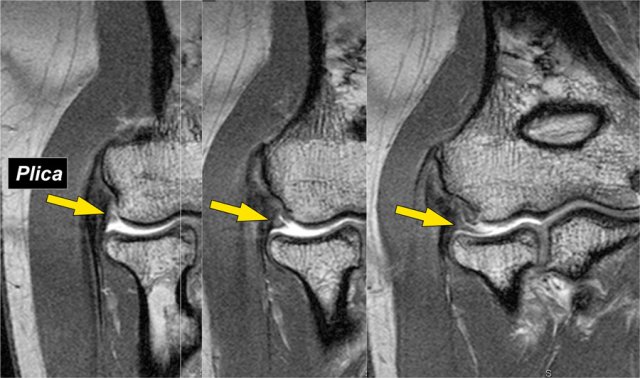

Plica

This structure on the lateral side of the joint is sometimes seen and is a plica.

It can be prominent and almost look like a meniscus.

It is a normal structure, but sometimes it is thickened or irregular and it may be a cause of symptoms.